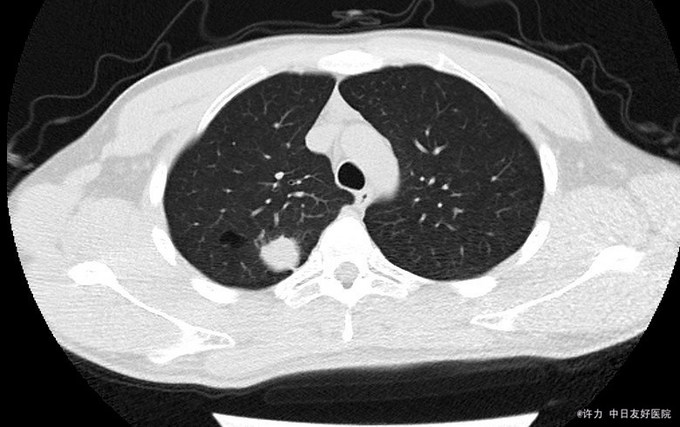

患者男,23岁,主因“肺良性肿瘤术后半月余复查”以“肺良性肿瘤”收入院。 患者诉2015年12月09日因右肺良性肿瘤在我院行胸腔镜右肺上叶楔形切除术,术后患者恢复良好,带胸腔引流管出院;今患者遵医嘱定期回院复查,我科以肺良性肿瘤术后复查收住入院

肺良性肿瘤术后

患者术后3周,胸引管有少量血性胸水引出